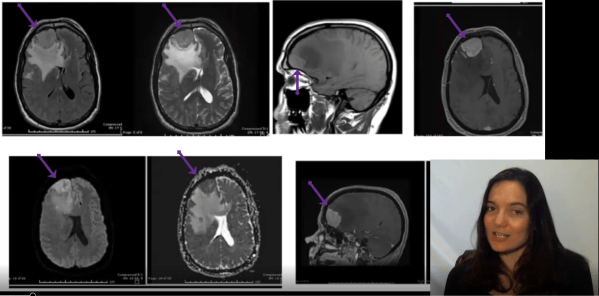

Video: Breast Cancer Metastasis to Brain

Join me for a narrated pathology review of breast cancer (ductal adenocarcinoma) metastatic to brain. https://youtu.be/EkRq-Vs5WoU